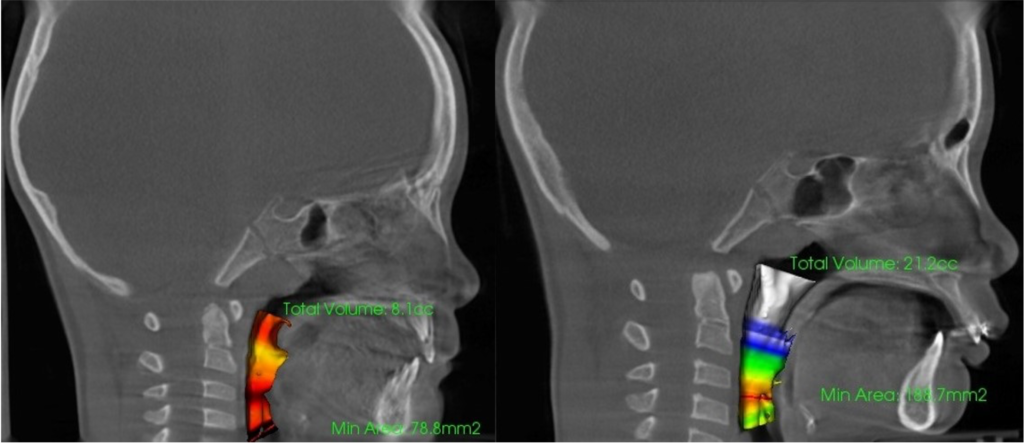

上下顎の劣成長は、空気の通り道である、気道や鼻腔を狭くしてしまいます。明確な症状として表出するかどうかには個人差もありますが、自覚症状の有無に関わらず、大多数の子どもたちは、常に酸素不足のリスクに晒されています。

治療によって、上顎が上がれば、下顎も連動して上がり、気道の圧迫から開放されます。そして舌の位置も上がり、上顎につきやすくなります。基本的に上顎の位置が上がり、骨格のゆがみが改善され、舌が上顎につくようになれば、歯とは自然と並びます。

耳鼻科とも連携し、気道や鼻腔の通気性、歯並び、骨格の変化を総合的に診査しながら、当院のランパセラピーはゴールへと向かいます。